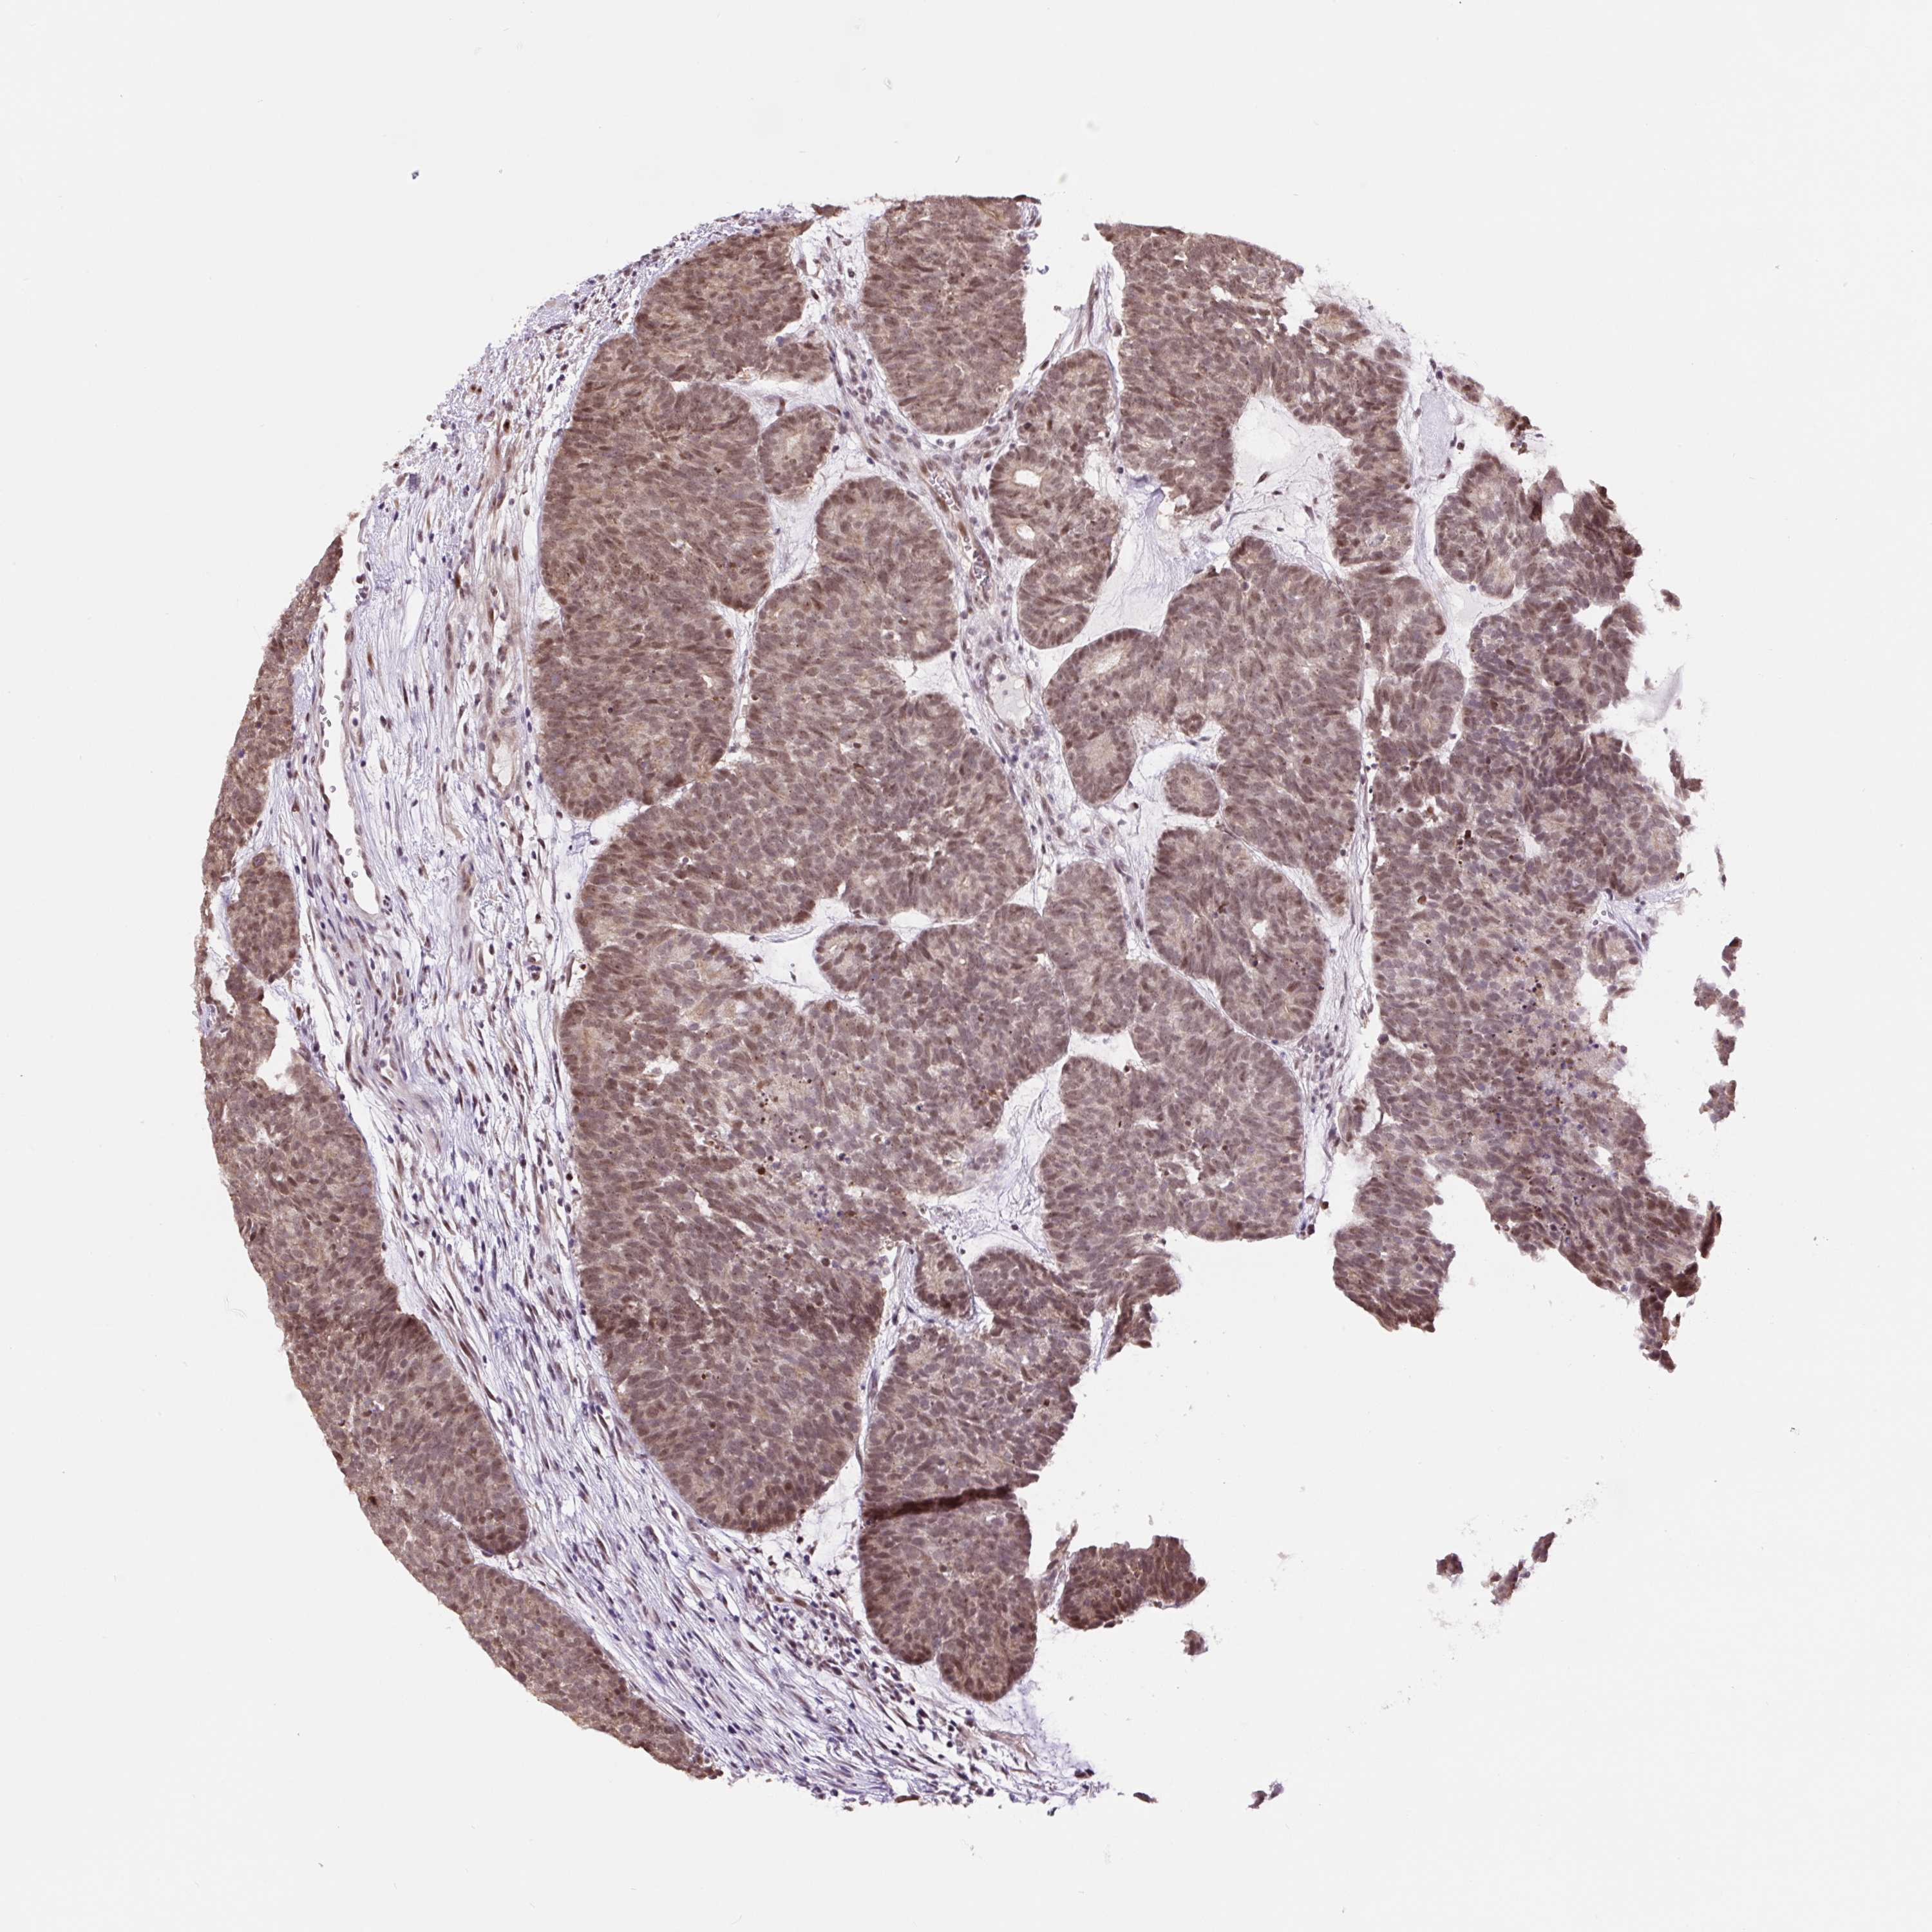

HEAD AND NECK CANCER - Protein expressioni

A mouse-over function shows sample information and annotation data. Click on an image to view it in a full screen mode. Samples can be filtered based on level of antibody staining by selecting one or several of the following categories: high, medium, low and not detected. The assay and annotation is described here.

Antibody stainingi

Antibody staining in the annotated cell types in the current human tissue is reported as not detected, low, medium, or high, based on conventional immunohistochemistry profiling in selected tissues. This score is based on the combination of the staining intensity and fraction of stained cells.

Each image is clickable and will lead to virtual microscopy that enables deeper exploration of all samples and also displays staining intensity scores, fraction scores and subcellular localization as well as patient and tissue information for each sample.

Antibody HPA054334

Staining

High

Medium

Low

Not detected

Intensity

Strong

Moderate

Weak

Negative

Quantity

>75%

75%-25%

<25%

None

Location

Nuclear

Cytoplasmic/membranous

Cytoplasmic/membranous,nuclear

Squamous cell carcinoma, NOS